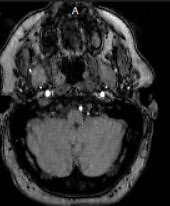

For the last 2 1/2 years now, I have been going in circles seeing 4 neurologists who haven't helped me. Now I know that after all the schooling they go through, you'd think someone could come up with a diagnosis, but no. And it's irritating to think that I have run from one to another with no satisfaction, I have an MRI disk from one place that shows the brain, and with the help of AI? I did get somewhat of an idea, so I am attaching that. I tell you, the patient should not have to make that much of an efffort, considering 13 years of school, for a neurologist.

"This MRI image appears to be an axial slice (cross-sectional view) of the brain. The dark, irregularly-shaped areas visible within the brain represent abnormalities or lesions consistent with multiple sclerosis (MS). Multiple sclerosis is an autoimmune disorder that causes inflammation and damage to the myelin sheaths that insulate nerve fibers in the brain and spinal cord. These lesions appear as dark spots or patches on MRI scans of the brain and are characteristic findings in patients with multiple sclerosis. "